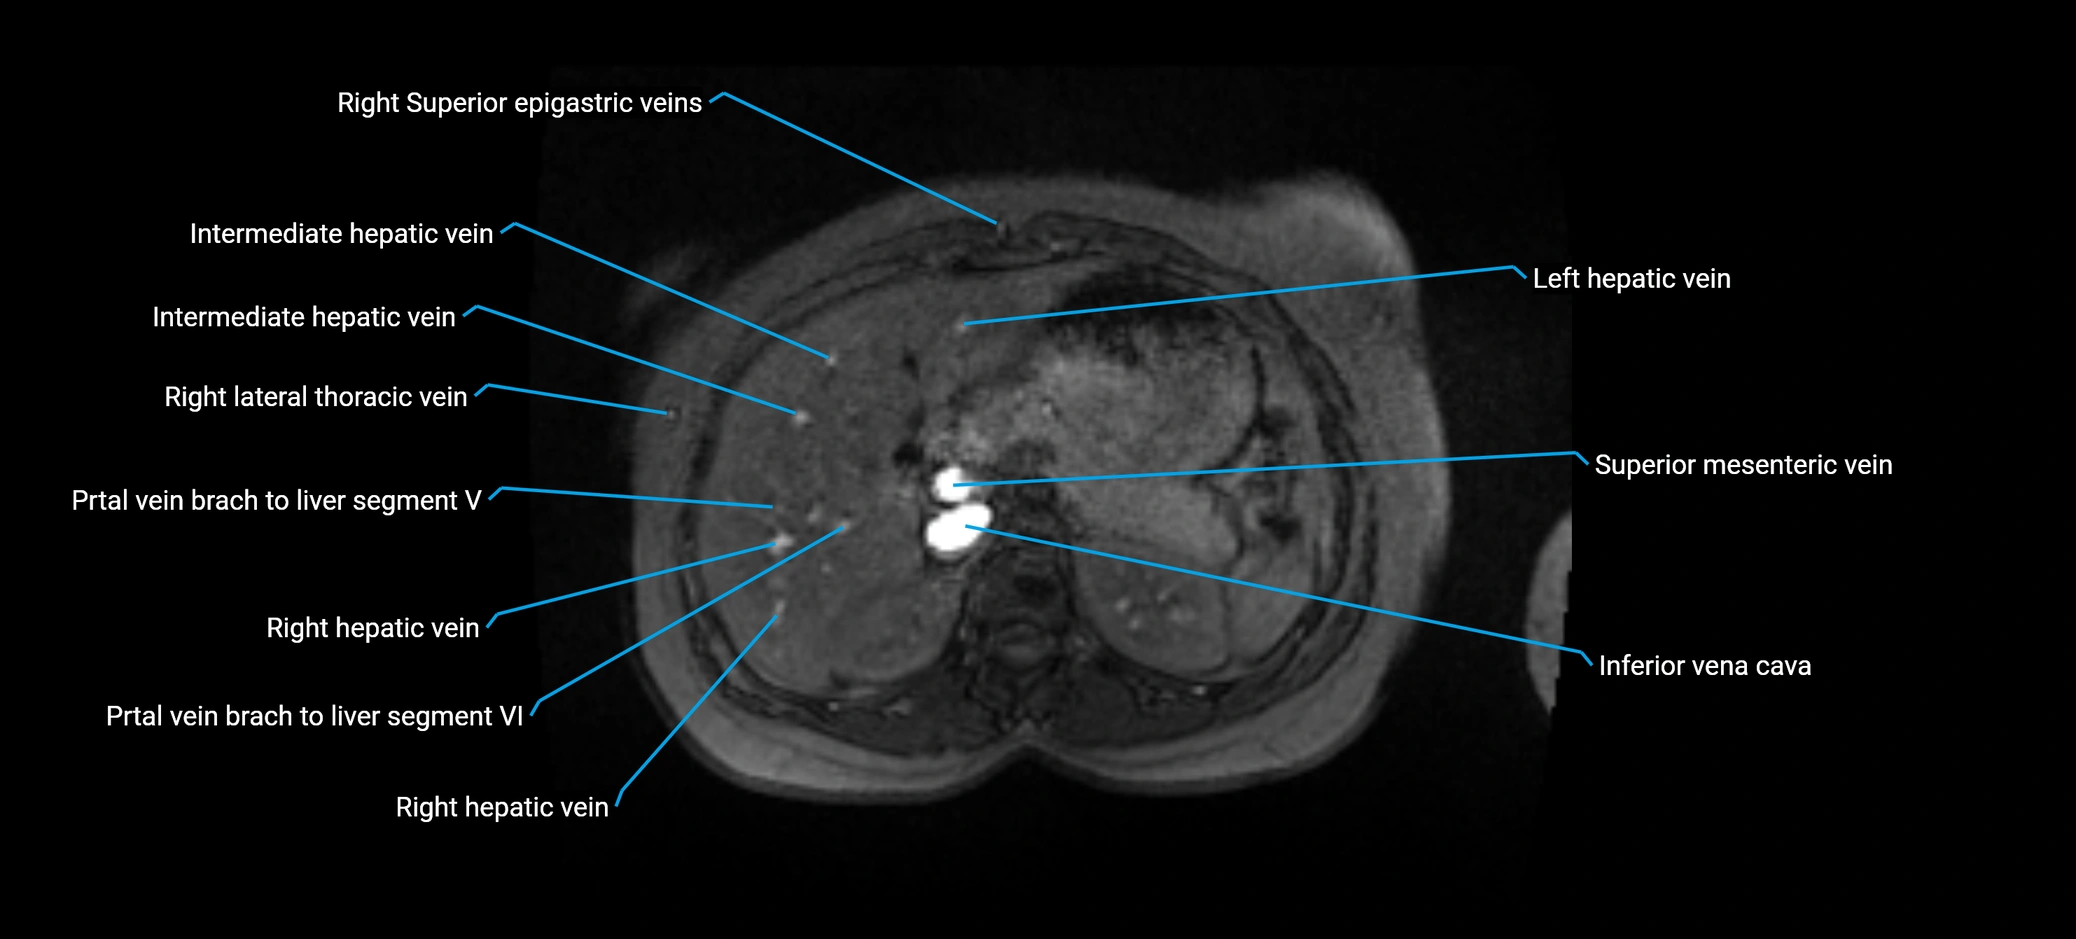

MRV TOF (Time-of-Flight MR Venography):

• Appears as a bright, high-signal vascular channel representing flowing blood

• Clearly shows branching pattern of right portal vein into anterior and posterior branches

• Best in coronal or axial reconstructions for segmental mapping

• No need for contrast, relies on flow-related enhancement

Post-Contrast T1 Fat-Sat GRE:

• Enhances brightly and homogeneously during the portal venous phase

• Clearly delineates branching into segments V and VIII

• Best sequence for evaluating patency, caliber, and anatomic variants

• Early arterial phase: minimal enhancement

• Delayed phase: gradual washout but still brighter than hepatic parenchyma

MRI image

image